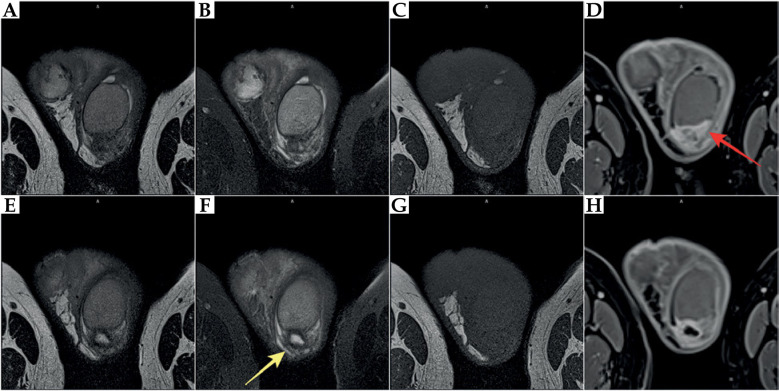

本文的目的是报道一例前列腺癌近距离放射治疗(BT)患者罕见的睾丸附睾炎并发症,该患者在BT治疗4周后行经输尿管前列腺切除术(TURP)。一位73岁的前列腺癌患者(中危组)符合高剂量率(HDR) BT联合雄激素剥夺治疗(ADT) 6个月(leuprorelin)的条件。由于BT术后尿潴留等症状加重,患者需要导尿。此外,下尿路和前列腺存在细菌性炎症。由于排尿障碍延长,行TURP,在BT完成4个月和TURP后拔管3个月后导致慢性睾丸附睾炎。由于长期炎症,治疗无效,切除左睾丸及左附睾。不幸的是,术后在床和左腹股沟出现炎症症状。由于这些不同程度的症状持续存在,因此引入了抗炎药和镇痛药。在HDR-BT后进行TURP过快可能会导致严重的并发症。对于接受BT治疗的患者,应慎用TURP,在BT后发生泌尿系统疾病时,必须采取保守和药物治疗,任何干预(TURP)应在BT后至少3-6个月进行,这一点尤其重要,因为随着时间的推移,辐射效应会逐渐发展。

The aim of this paper was to present a rare complication of orchiepididymitis in a patient treated with brachytherapy (BT) for prostate cancer, who underwent trans-ureteral resection of the prostate (TURP) four weeks after BT. A 73-year-old patient with prostate cancer (intermediate-risk group) was eligible for high-dose-rate (HDR) BT combined with androgen deprivation therapy (ADT) for 6 months (leuprorelin). Due to increased symptoms, such as urinary retention after BT, the patient required catheterization. Additionally, bacterial inflammation in the lower urinary tract and prostate was present. Due to prolonged micturition disorders, TURP was performed, leading to chronic orchiepididymitis four months after completion of BT and three months after catheter removal following TURP. Due to long-term inflammation, which was resistant to treatment, the left testicle with left epididymis was removed. Unfortunately, inflammatory symptoms occurred post-operatively in the bed and the left groin. Since these symptoms of varying severity continued, anti-inflammatory drugs and analgesics were introduced. TURP performed too quickly after HDR-BT might cause severe complications. Extreme caution regarding TURP should be exercised in patients undergoing BT. Conservative and pharmacological treatment must be introduced in the occurrence of urinary disorders after BT, and any intervention (TURP) should be performed at least 3-6 months after BT. This is especially crucial because of the development of radiation effect over time.